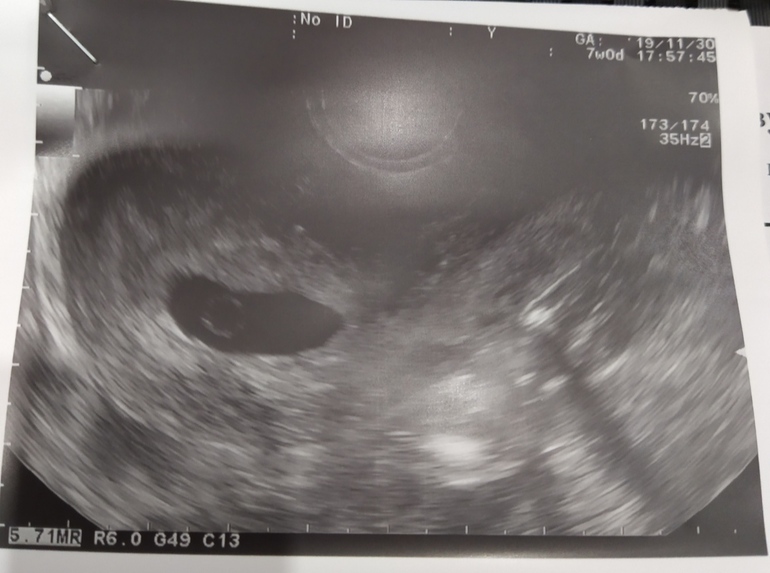

Tasha

В 8 недель увидели пустое плодное яйцо 19мм. Тоже сказали, что можно не надеяться, желточного мешочка тоже не было. Через неделю УЗИ - пя 23мм - пустое. Сказали если пя 23мм и выше и в нем ничего нет, то это 100% анэмбриония... Но я ждала ещё неделю, надеялась на чудо, но нет, следующее УЗИ ничего не показало тоже.